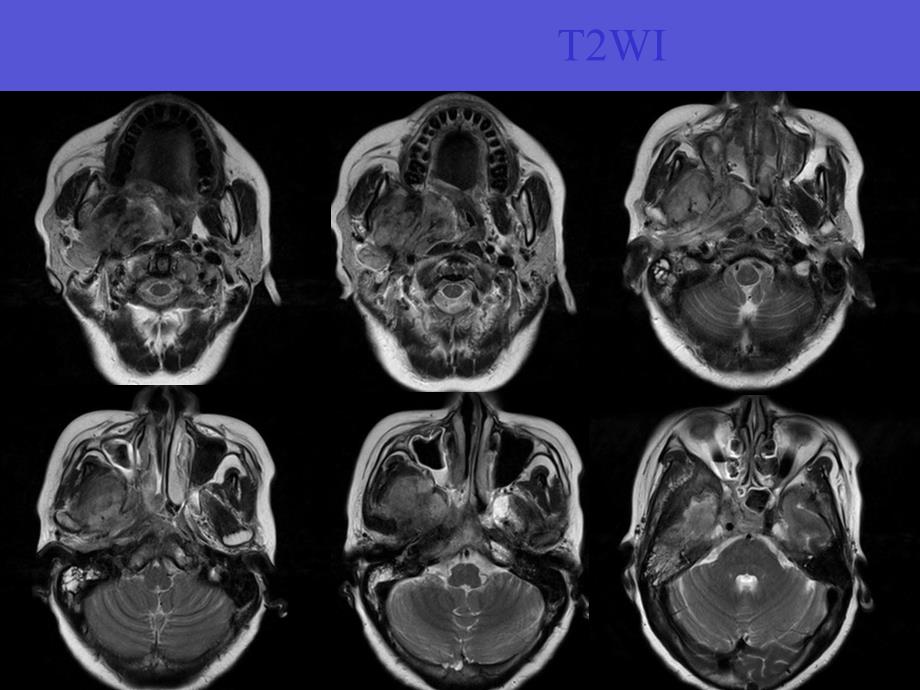

1、病例1患者女,58岁,口咽异物感,吞咽不畅,右颈部疼痛不适2个月无发热、盗汗及体重减轻,无咳嗽、咳痰,无明确既往病史查体:右软腭膨隆,口咽腔缩小,右颌面部肌肉略压痛鼻咽镜:鼻咽部右侧可见粘膜膨隆突出,右侧软腭膨隆 T2WIT1WIFS-T2WIGd-TraGd-SagGd-CorCT病理结果孤立性纤维性肿瘤,浸润生长,累计横纹肌组织孤立性纤维性肿瘤 孤立性纤维性肿瘤由(solitary fibrous tumor,SFT)由Klemperer和Rabin于1931年首先在胸膜发现并命名 SFT 是一种起源于CD34 阳性的树突状间叶细胞的肿瘤,并具有向纤维母细胞、肌纤维母细胞分化的特征 胸膜以

3、其临床症状差异很大,早期常表现为毫无临床症状的缓慢增大的肿块。临床上多数病例为缓慢生长的无痛性包块;特殊部位者可有相应压迫症状,少数直径较大者可产生副肿瘤综合症影像学特点 SFT CT平扫表现为边界清楚、密度均匀、与周围软组织等密度的孤立性软组织肿块;无分叶或可见浅小分叶;一般肿块内部无钙化;邻近骨结构无明显的骨质破坏;增强扫描实质一般明显强化 CT上明显的骨质破坏则反映了病变有恶性生物学行为 SFT 在MRI 上表现为T1WI 上以低信号为主,T2WI 上为低或中低混杂信号为主,增强后不均匀强化 其信号改变与病理成分相对应,SFT 瘤体内常含有丰富的纤维组织、透明样变性、黏液样变性、囊性变及

4、出血等,黏液样变或囊变坏死区呈高信号,细胞密集区呈稍高信号,低信号区反映致密胶原纤维鉴别诊断1、鼻咽癌 鼻咽癌是源于鼻咽部上皮组织的一种恶性肿瘤 大多于4060岁发病,男多于女,血涕是最常见的早期症状 NPC好发于鼻咽部侧隐窝的黏膜表层,使局部黏膜增厚或形成小肿块,至鼻咽腔不对称变浅、变窄。肿瘤组织的信号强度较均匀,T1WI 呈较肌肉略低信号,T2WI 呈略高信号,Gd-DTPA 增强后肿块明显强化。部分可呈肿块样突入鼻咽腔,或向黏膜下生长突入咽旁间隙的内后方;部分可呈浸润性生长,肿瘤与周围结构分界不清,脂肪间隔消失,局部骨质可有破坏 NPC可早期发生淋巴结转移,甚至鼻咽部的肿瘤处于影像学和鼻